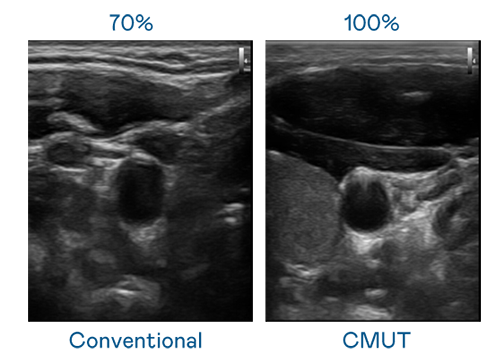

CMUT 技术是一种用电容式微机电元件来产生超音波讯号的技术。与传统 PZT 压电式技术相比,CMUT 频宽增加 30%,更宽频的超音波讯号让影像解析度大幅提升,是实现高影像品质医疗超音波扫描、促进精准医疗发展的关键技术。

大频宽带来超清晰影像

超音波影像的解析度高低,首先取决于探头能发出的讯号频宽。Ag尊龙凯时 CMUT 可提供高清晰的超音波讯号,提供高频宽、高灵敏度、影像纹理细节更高的超音波影像,协助医护人员缩短影像判读时间及利用精准的医疗影像进行诊断。